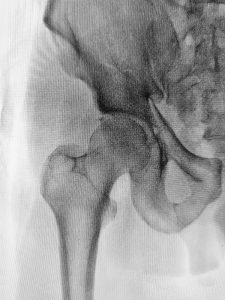

With life expectancy increasing it is becoming more evident that bone health and fall prevention are key to a good quality of life. Osteoporosis is defined as a decrease in bone mass or a change in the structure of the bone causing the bone to be more fragile.1 If the bone is weak there is a higher chance of a fracture (bone break). The most common areas of fractures are the hip, spine, forearm, and humerus (upper arm bone). Osteoporosis causes more than 8.9 million fractures annually worldwide, affecting predominantly postmenopausal women. The probability of women, at menopause, of having an osteoporotic fracture exceeds that of breast cancer and the likelihood of a fracture is approximately 40%.2

The important take-home message is to try and modify the risk factors that you have control over, especially if you have genetic factors or medical conditions that increase your risk. The consequence of having osteoporosis is a higher chance of developing a fracture. An osteoporotic fracture can be characterized if it results from a low-energy fall. Low energy is defined as a fall from a standing height or less, or trauma that in a healthy individual would not cause a fracture.3 It is important to understand your fall risk and make sure to modify factors to increase your safety and prevent a fall. A physical therapist has a variety of fall risk assessment tests they can administer to provide patients with a quantifiable measure of their fall risk. A physical therapist can also provide a specific exercise program that is individualized based on the type of balance deficit found on your initial or subsequent visits. It is also important to modify the home environment for safety.